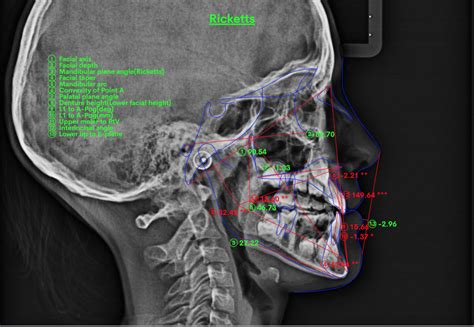

Análisis Cefalométrico y Radiografía Panorámica

El análisis cefalométrico es una herramienta diagnóstica utilizada en ortodoncia para evaluar las relaciones esqueléticas y dentales del cráneo y la cara. Se basa en la medición de puntos y ángulos específicos en una radiografía lateral de cráneo. La radiografía panorámica, por su parte, proporciona una visión general de los dientes, los maxilares y las estructuras adyacentes.